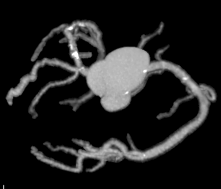

Công nghệ tim mạch Aheart

Phương pháp chỉnh sửa ECG

Hình ảnh lâm sàng